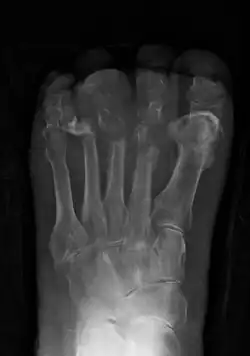

Osteomyelitis

| Osteomyelitis of the 1st toe | |